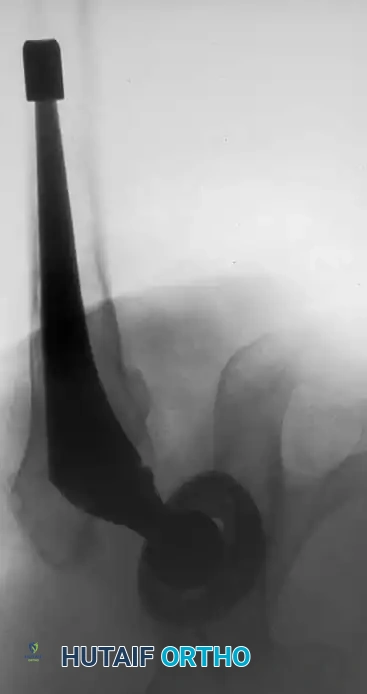

Associated Surgical & Radiographic Imaging